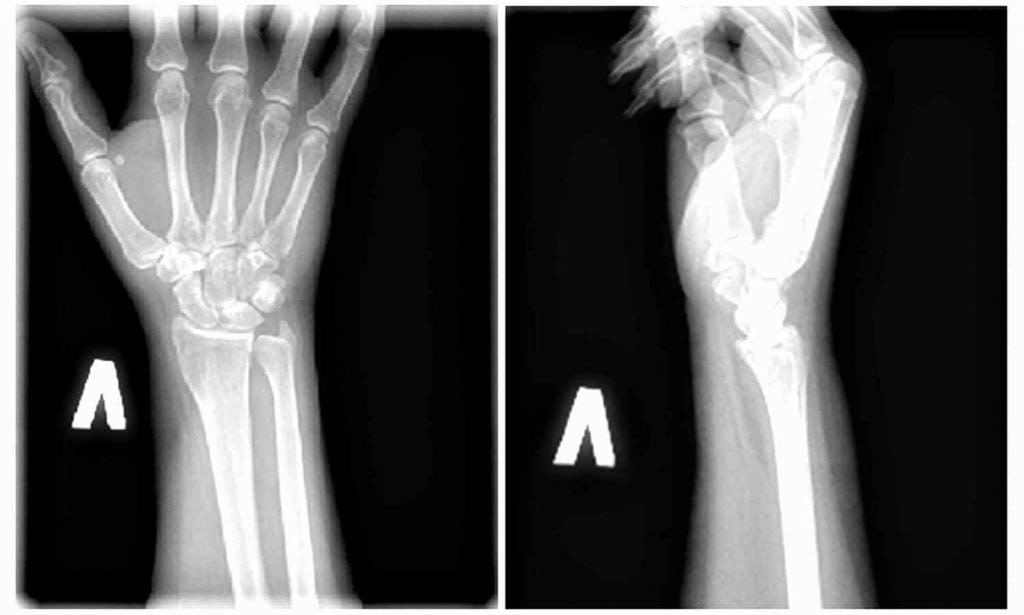

Опытный ревматолог или травматолог может поставить диагноз при первичном осмотре пациента на основании его жалоб и изучения анамнеза. При вялотекущем воспалительном процессе иногда требуется проведение дополнительных исследований:

- рентгенографии;

- компьютерной или магнитно-резонансной томографии;

- ультразвукового исследования.